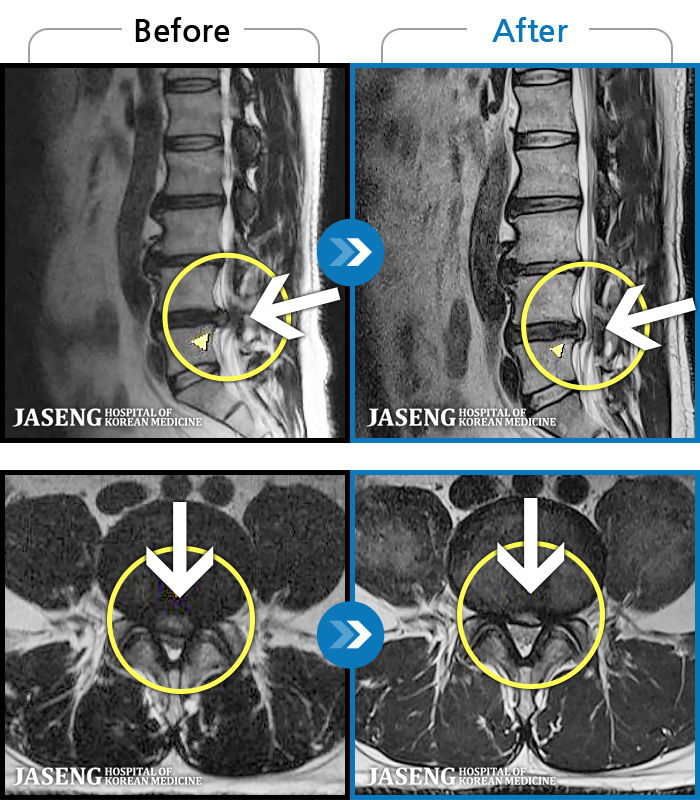

1,240 MRI ũ ʸ Ȯϼ.

[ؿ] 24.10.10~25.04.23